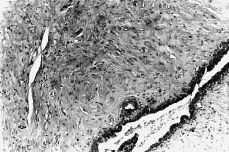

El examen histológico de la pieza informa de estructuras glandulares comprimidas por una gran proliferación colágena, tapizadas por un epitelio cúbico y cilíndrico según zonas, adoptando estructuras caprichosas por la proliferación fibroblástica periglandular.

Presenta inmunohistoquimia positiva para los receptores de estrógenos y progesterona. La tinción EMA tiñe positivamente la secrección glandular. Según esto, el diagnóstico anatomopatológico confirma un fibroadenoma de vulva.

Figura 1.